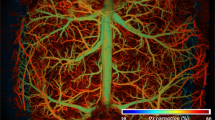

To demonstrate the advantages of the PIN-PMN-PT-based TUT for PAM imaging, we mapped the vasculature of a mouse ear in vivo, utilizing both PIN-PMN-PT and LN-based TUTs for comparison. A 532 nm pulsed laser was focused on the mouse ear through TUTs to excite the PA signals from the hemoglobin in red blood cells, thus enabling tracking and mapping of the vascular anatomy. Figure 5a shows the photoacoustic image of a 4 mm × 4 mm area captured by the PIN-PMN-PT-based TUT. The image was normalized logarithmically and displayed in a dynamic range of 40 dB. A densely packed capillary vessel network can be clearly imaged. The entangled concomitant venules and arterioles are observed and indicated by the white arrows58. The imaging depth is ~ 0.5 mm from the surface of the tissues. The maximum imaging depth is limited to ∼ 1 mm due to optical scattering in tissues42. Figure 5b shows the locally enlarged image of a bifurcation of arterial and venous trees in the area marked by a box in Fig. 5a. Figure 5c shows the PA intensity profiles of individual vessels in representative B-scans positioned by the white dash line in Fig. 5b. The diameter of the smallest vessel that can be distinguished from Fig. 5c is 13 μm, indicating a good lateral resolution of the PIN-PMN-PT-based TUT. To make a side-by-side comparison, the same area was imaged by the LN-based TUT, and the results are shown in Fig. 5d–f. Most of the PA signals from the complicated and detailed capillaries are overwhelmed by the background noise due to the poor sensitivity of the LN-based TUT (Fig. 5d). Clearly, only the major vessels with a diameter larger than 20 μm can be distinguished, as indicated by the red arrows in Fig. 5e, f. The small vessels marked by the blue arrows in Fig. 5b, c cannot be resolved by the LN-based TUT. This is also evidenced by the analysis of the vessel distribution. The total vessel density captured by the PIN-PMN-PT-based TUT is more than three times higher than that captured by the LN-based TUT (Supplementary Fig. 22). Meanwhile, the proportion of detected vessels with diameter below 20 μm is increased by 30%. Of particular significance is that the SNR of the PIN-PMN-PT-based TUT is calculated to be 18 dB from the in vivo imaging result, more than 13 dB higher than that of the LN-based TUT (Supplementary Fig. 23). We also noticed that the background noise levels from the photoacoustic images captured by LN and PIN-PMN-PT transducers are similar, suggesting that the improved SNR in PIN-PMN-PT-based TUT is mainly attributed to its higher PA sensitivity in contrast to LN-based TUT.

a Photoacoustic image of subcutaneous microvasculature networks in a mouse ear captured by the PIN-PMN-PT-based TUT. The white arrows indicate the bifurcations of venules and arterioles. b Locally enlarged image of the area positioned by the dashed line box in (a). c Normalized PA intensity with respect to lateral distance at the position marked by the white dash line in (b). The colored arrows in (b and c) indicate the vessels and corresponding PA intensity profiles, respectively. The vessel diameter was calculated by the full width at half maximum (FWHM) of the PA intensity profile. d Photoacoustic images captured by the LN-based TUT. e Locally enlarged image of the area positioned by the dashed line box in (d). f PA intensity at the position marked by the white dash line in (e). The red arrows highlight the vessels that are resolved by both PIN-PMN-PT- and LN-based TUTs, while the blue arrows highlight the vessels that cannot be clearly resolved by the LN-based TUT.

To demonstrate the potential of TUT for the fundamental research of brain science, we employed our newly developed PIN-PMN-PT-based TUT to visualize the dynamic change of the cerebral cortex microvasculature of a mouse with partial craniectomy, as schematically shown in Fig. 6a. Symptoms of epilepsy are produced by the intraperitoneal injection of Pentylenetetrazol (PTZ) solution59. Two-dimensional laser scanning was performed through the TUT. A laser repetition rate of 50 kHz provides a B-scan rate of 200 Hz with 250 A-lines, resulting in an acquisition time of 1.25 s for a 250 × 250-pixel image. Figure 6b and c show eight representative images illustrating the cortex vasculature at different time points. Prior to the injection, the vasculature was in a normal state and basically remained unchanged. Following the injection, the vessels exhibited dynamic contractions and expansions due to the drug-induced epilepsy. To quantitatively analyze the dynamic changes of the vessels, we calculated the vessel diameter at each frame, as shown in Fig. 6d. Within the initial 20 s, the vessel diameter was kept at ~ 30 μm. However, following the injection, the vessel diameter experienced abrupt reduction at intervals ranging from 5 to 15 s. In each spasm cycle, the vessel first contracted from 30 μm to 15 μm, then expanded to 50 μm before returning to its original size of 30 μm, where each cycle lasted about 3–5 s. These findings indicate that the PIN-PMN-PT-based TUT holds great potential as a powerful tool for hemodynamics studies.

a Schematic diagram of a mouse with a cranial window. The Pentylenetetrazol (PTZ) solution was injected into the mouse to induce an epileptic seizure. The laser was focused on the cerebral cortex through the TUT and performed a fast 2D optical scan. b, c Changes of the cortex vasculature over time at normal and epileptic states, respectively. d Vessel diameters with respect to the time before and after the injection. The vessel diameter was calculated at the position marked by the green line in (b). e, f Detailed views of the regions marked by the blue and orange boxes in (d), where the dots highlighted the time points corresponding to the images in (b).